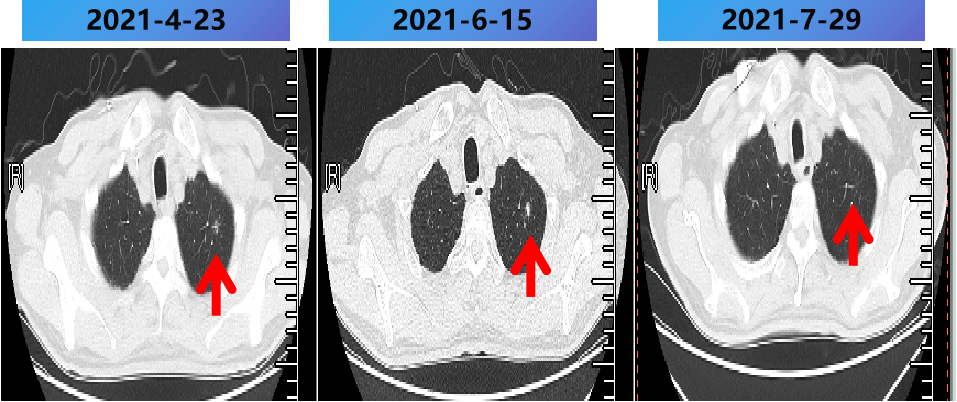

2021-2-25至2021-7-25 更换方案为bev+伊立替康+雷替曲塞 9周期,肺内病灶稳定(SD)。